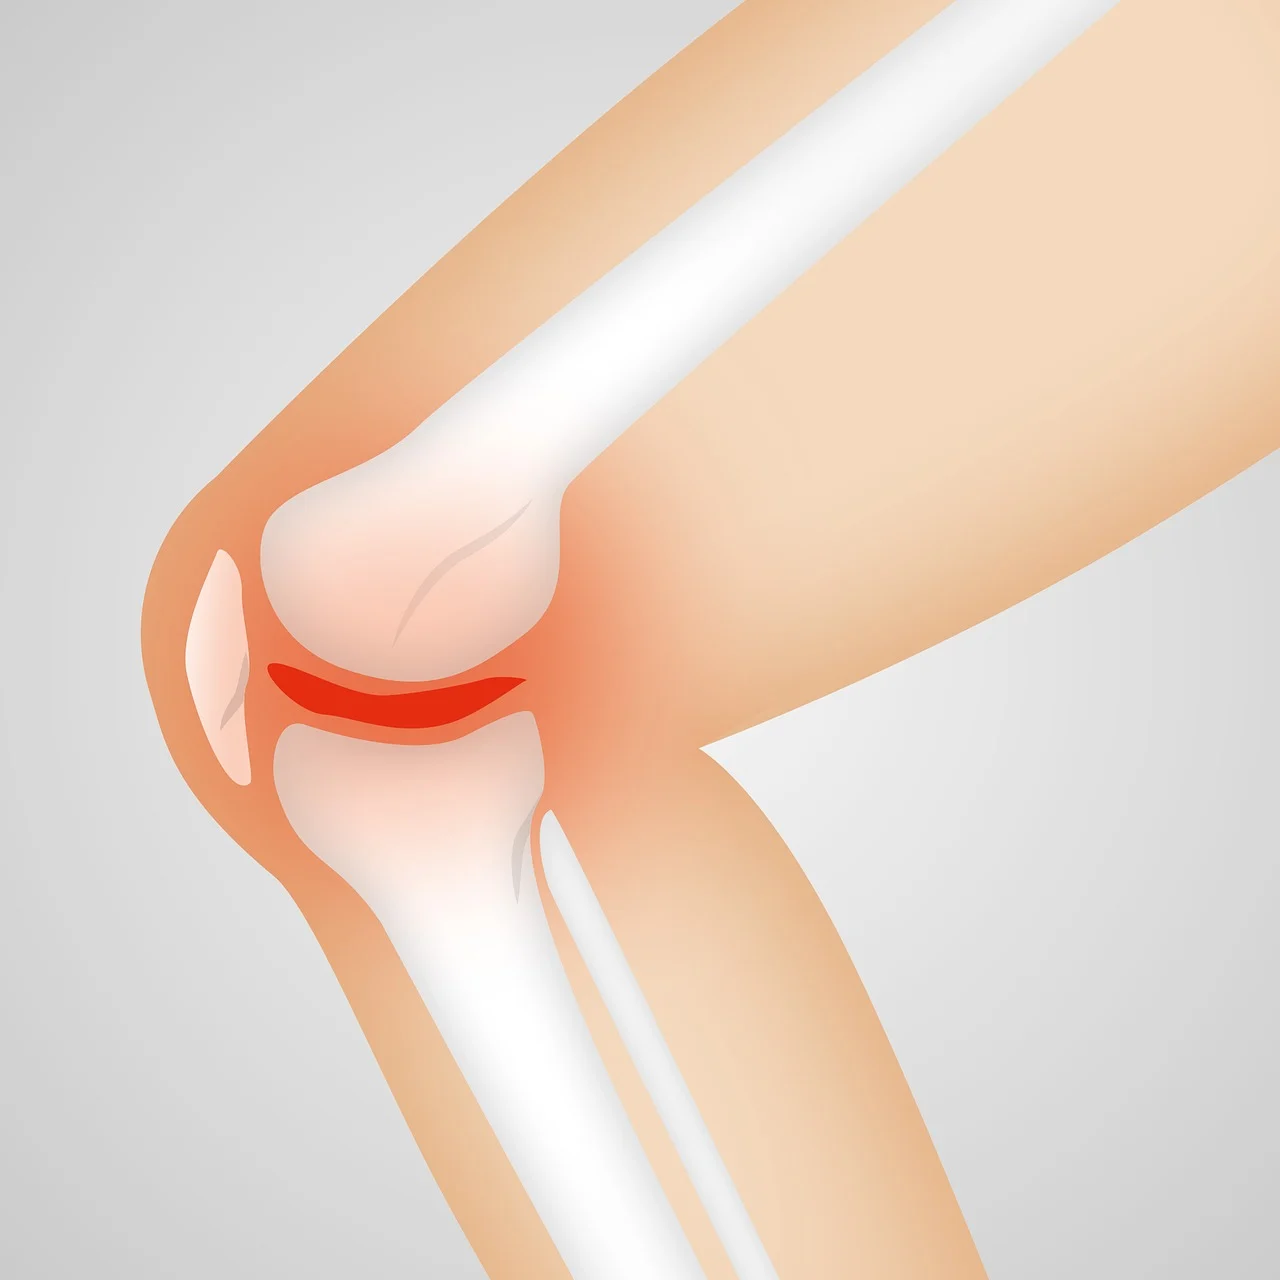

관절염은 관절의 염증으로 인해 발생하는 질환으로, 다양한 유형과 원인이 있습니다. 관절염은 전 세계적으로 수백만 명에게 영향을 미치며, 통증과 불편함을 유발하여 삶의 질을 저하시킬 수 있습니다. 대표적인 관절염의 유형은 골관절염(Osteoarthritis)과 류마티스 관절염(Rheumatoid Arthritis)입니다.

- 골관절염(Osteoarthritis): 연골이 점차적으로 닳아 없어지는 퇴행성 질환으로, 주로 노화나 반복적인 사용으로 인해 발생합니다. 무릎, 엉덩이, 손가락 관절에 주로 발생합니다.

- 류마티스 관절염(Rheumatoid Arthritis): 자가면역 질환으로, 면역 체계가 자신의 관절을 공격하여 염증을 일으킵니다. 전신에 걸쳐 여러 관절에 영향을 미치며, 피로와 전신적인 염증을 동반할 수 있습니다.